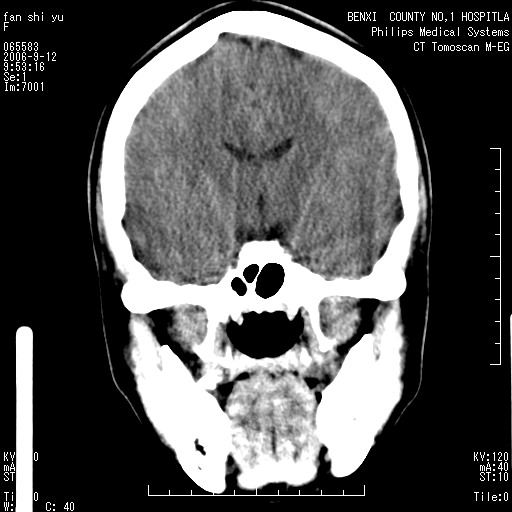

标题: CT4607:看看这个头颅冠状位。

女,22岁,自觉头顶部质硬包块.

巨大蛛网膜粒压迹。

巨大蛛网膜粒压迹